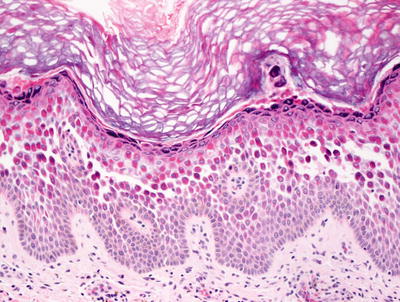

3.10.2 Histology

Histologic sections show skin with marked hyperkeratosis and focal parakeratosis (Fig. 3.25). The epidermis is acanthotic with elongation of the rete ridges. Dyskeratotic keratinocytes are frequent with corps ronds and grains that are easy to find in most cases (Fig. 3.26). Spongiosis is present focally, but it is not a prominent feature. There is no significant underlying inflammatory response in most cases.

Fig. 3.25

Hyperkeratosis and hypergranulosis are present in Darier disease. Foci of intra-epidermal acantholysis are present resulting in suprabasilar blister formation

Fig. 3.26

Abundant corps ronds and grains are present in the setting of a suprabasilar acantholytic blister in Darier disease